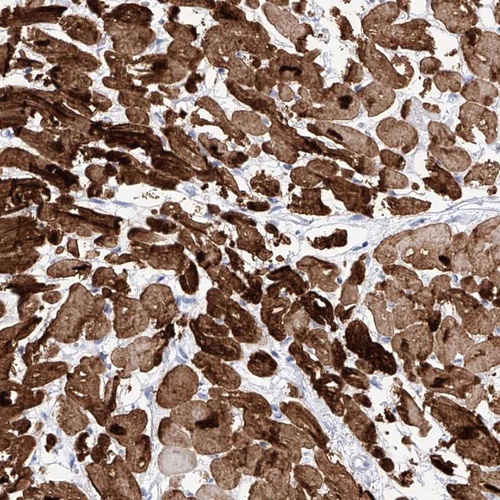

Immunohistochemical staining of human heart muscle shows strong cytoplasmic and nuclear positivity in myocytes.